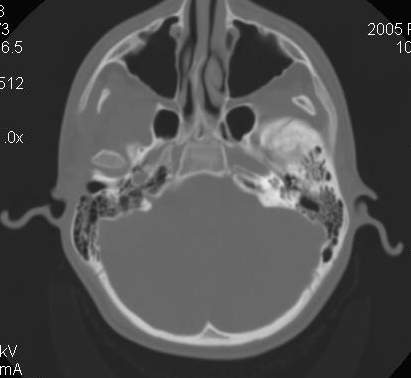

Пациент В., 13 лет. Диагноз: Костный анкилоз левого височно-нижнечелюстного сустава (ВНЧС), левосторонняя микрогения. Болеет с 2-х летнего возраста. Возможная причина развития анкилоза – воспалительный процесс (в первые 1,5 года жизни часто болел простудными заболеваниями, травму родители отрицают). В 3 и 5 лет проводилась редрессация – безуспешно. Прилагаются: ортопантомограмма, кадры СКТ с 3Д реконструкцией. Вопросы: определение тактики лечения – вид и сроки реконструктивно-пластической операции (этапов операции), а именно – неоартропластики и устранения микрогении, медикаментозная терапия в до- и послеоперационный период, ортодонтическое лечение.